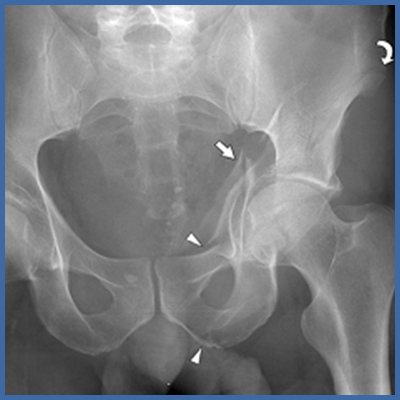

Verletzung des linken Beckenknochens; genauer des linken Hüftgelenkes. Der tragende Anteil der Hüftpfanne wurde durch die Wucht des Oberschenkelkopfes eingedrückt und zerborsten.